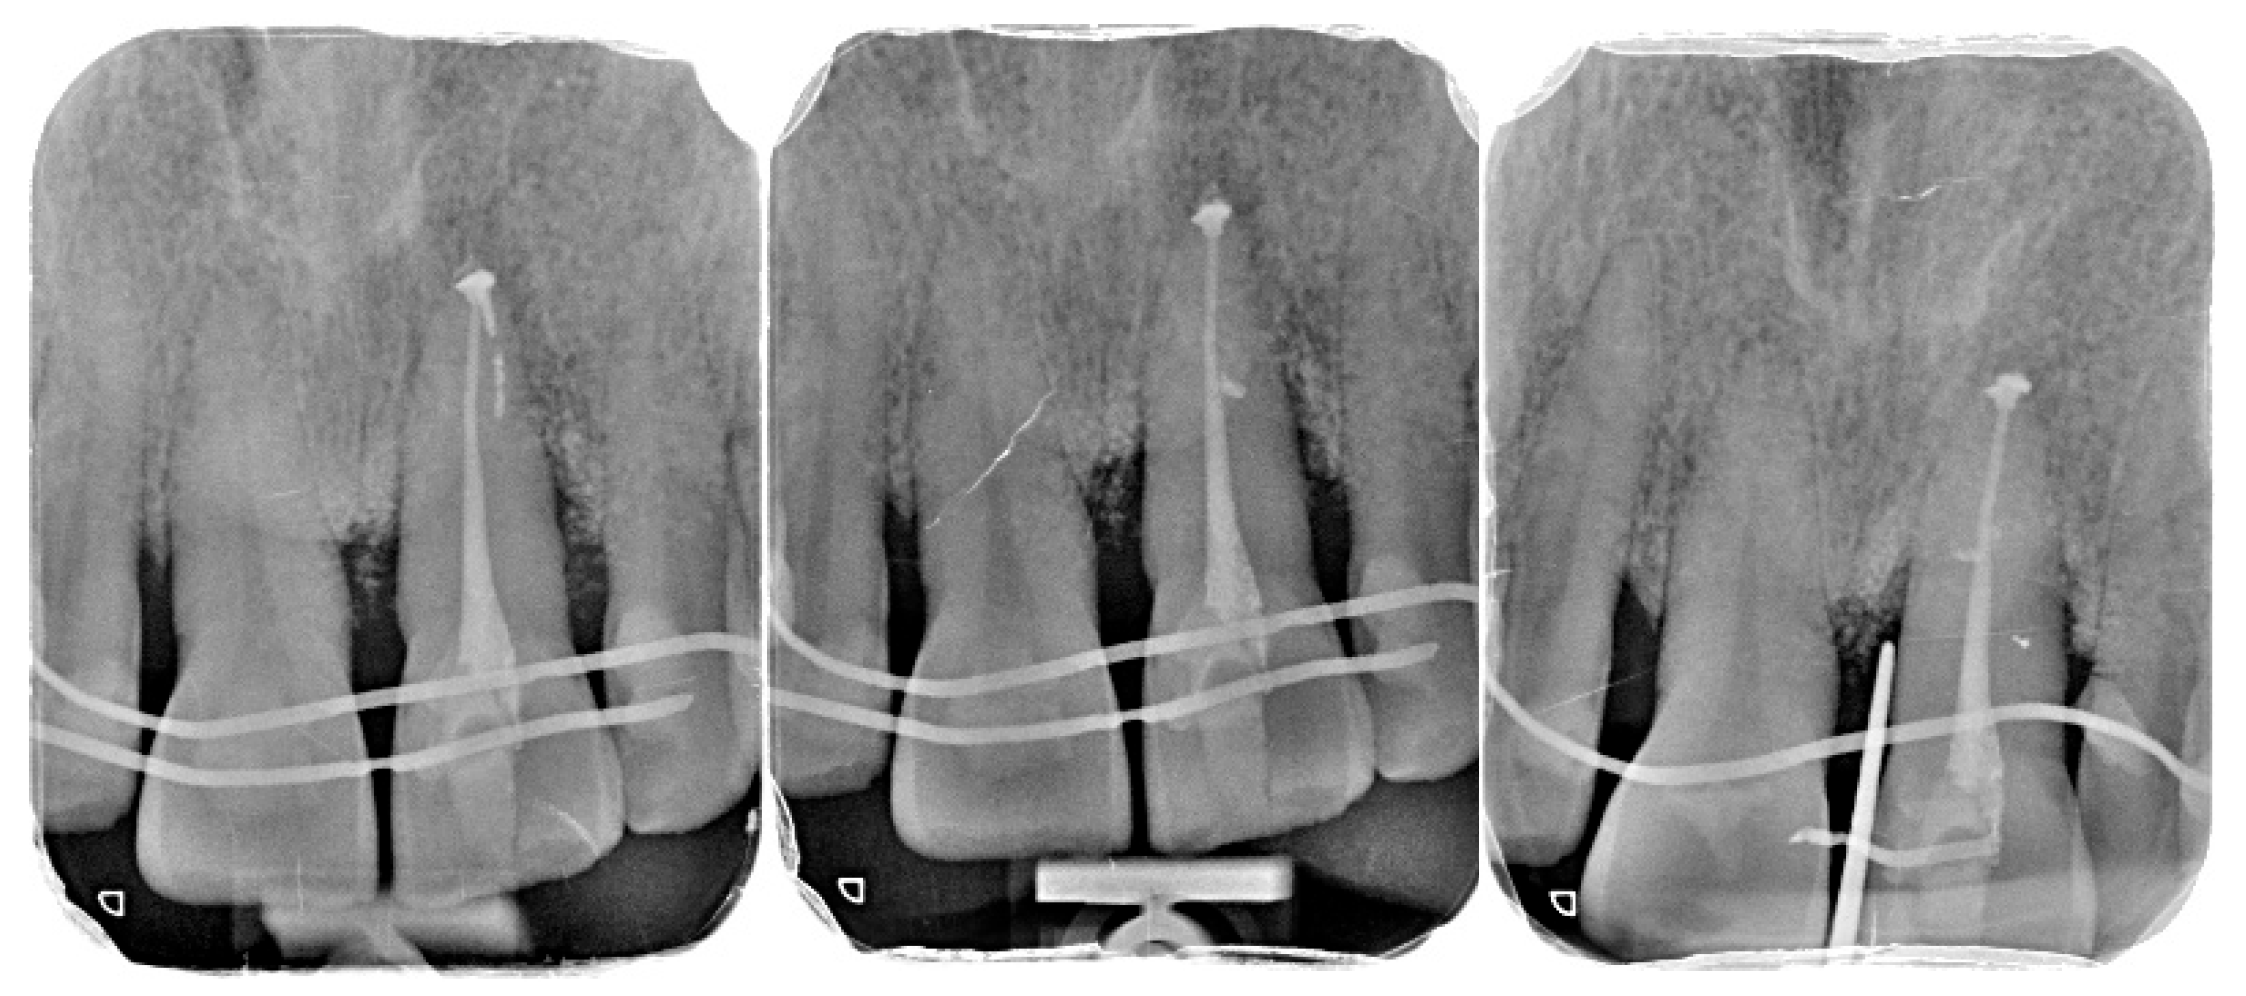

2.6. Postoperative Management and Endodontic Treatment

3.2. Radiographic Findings